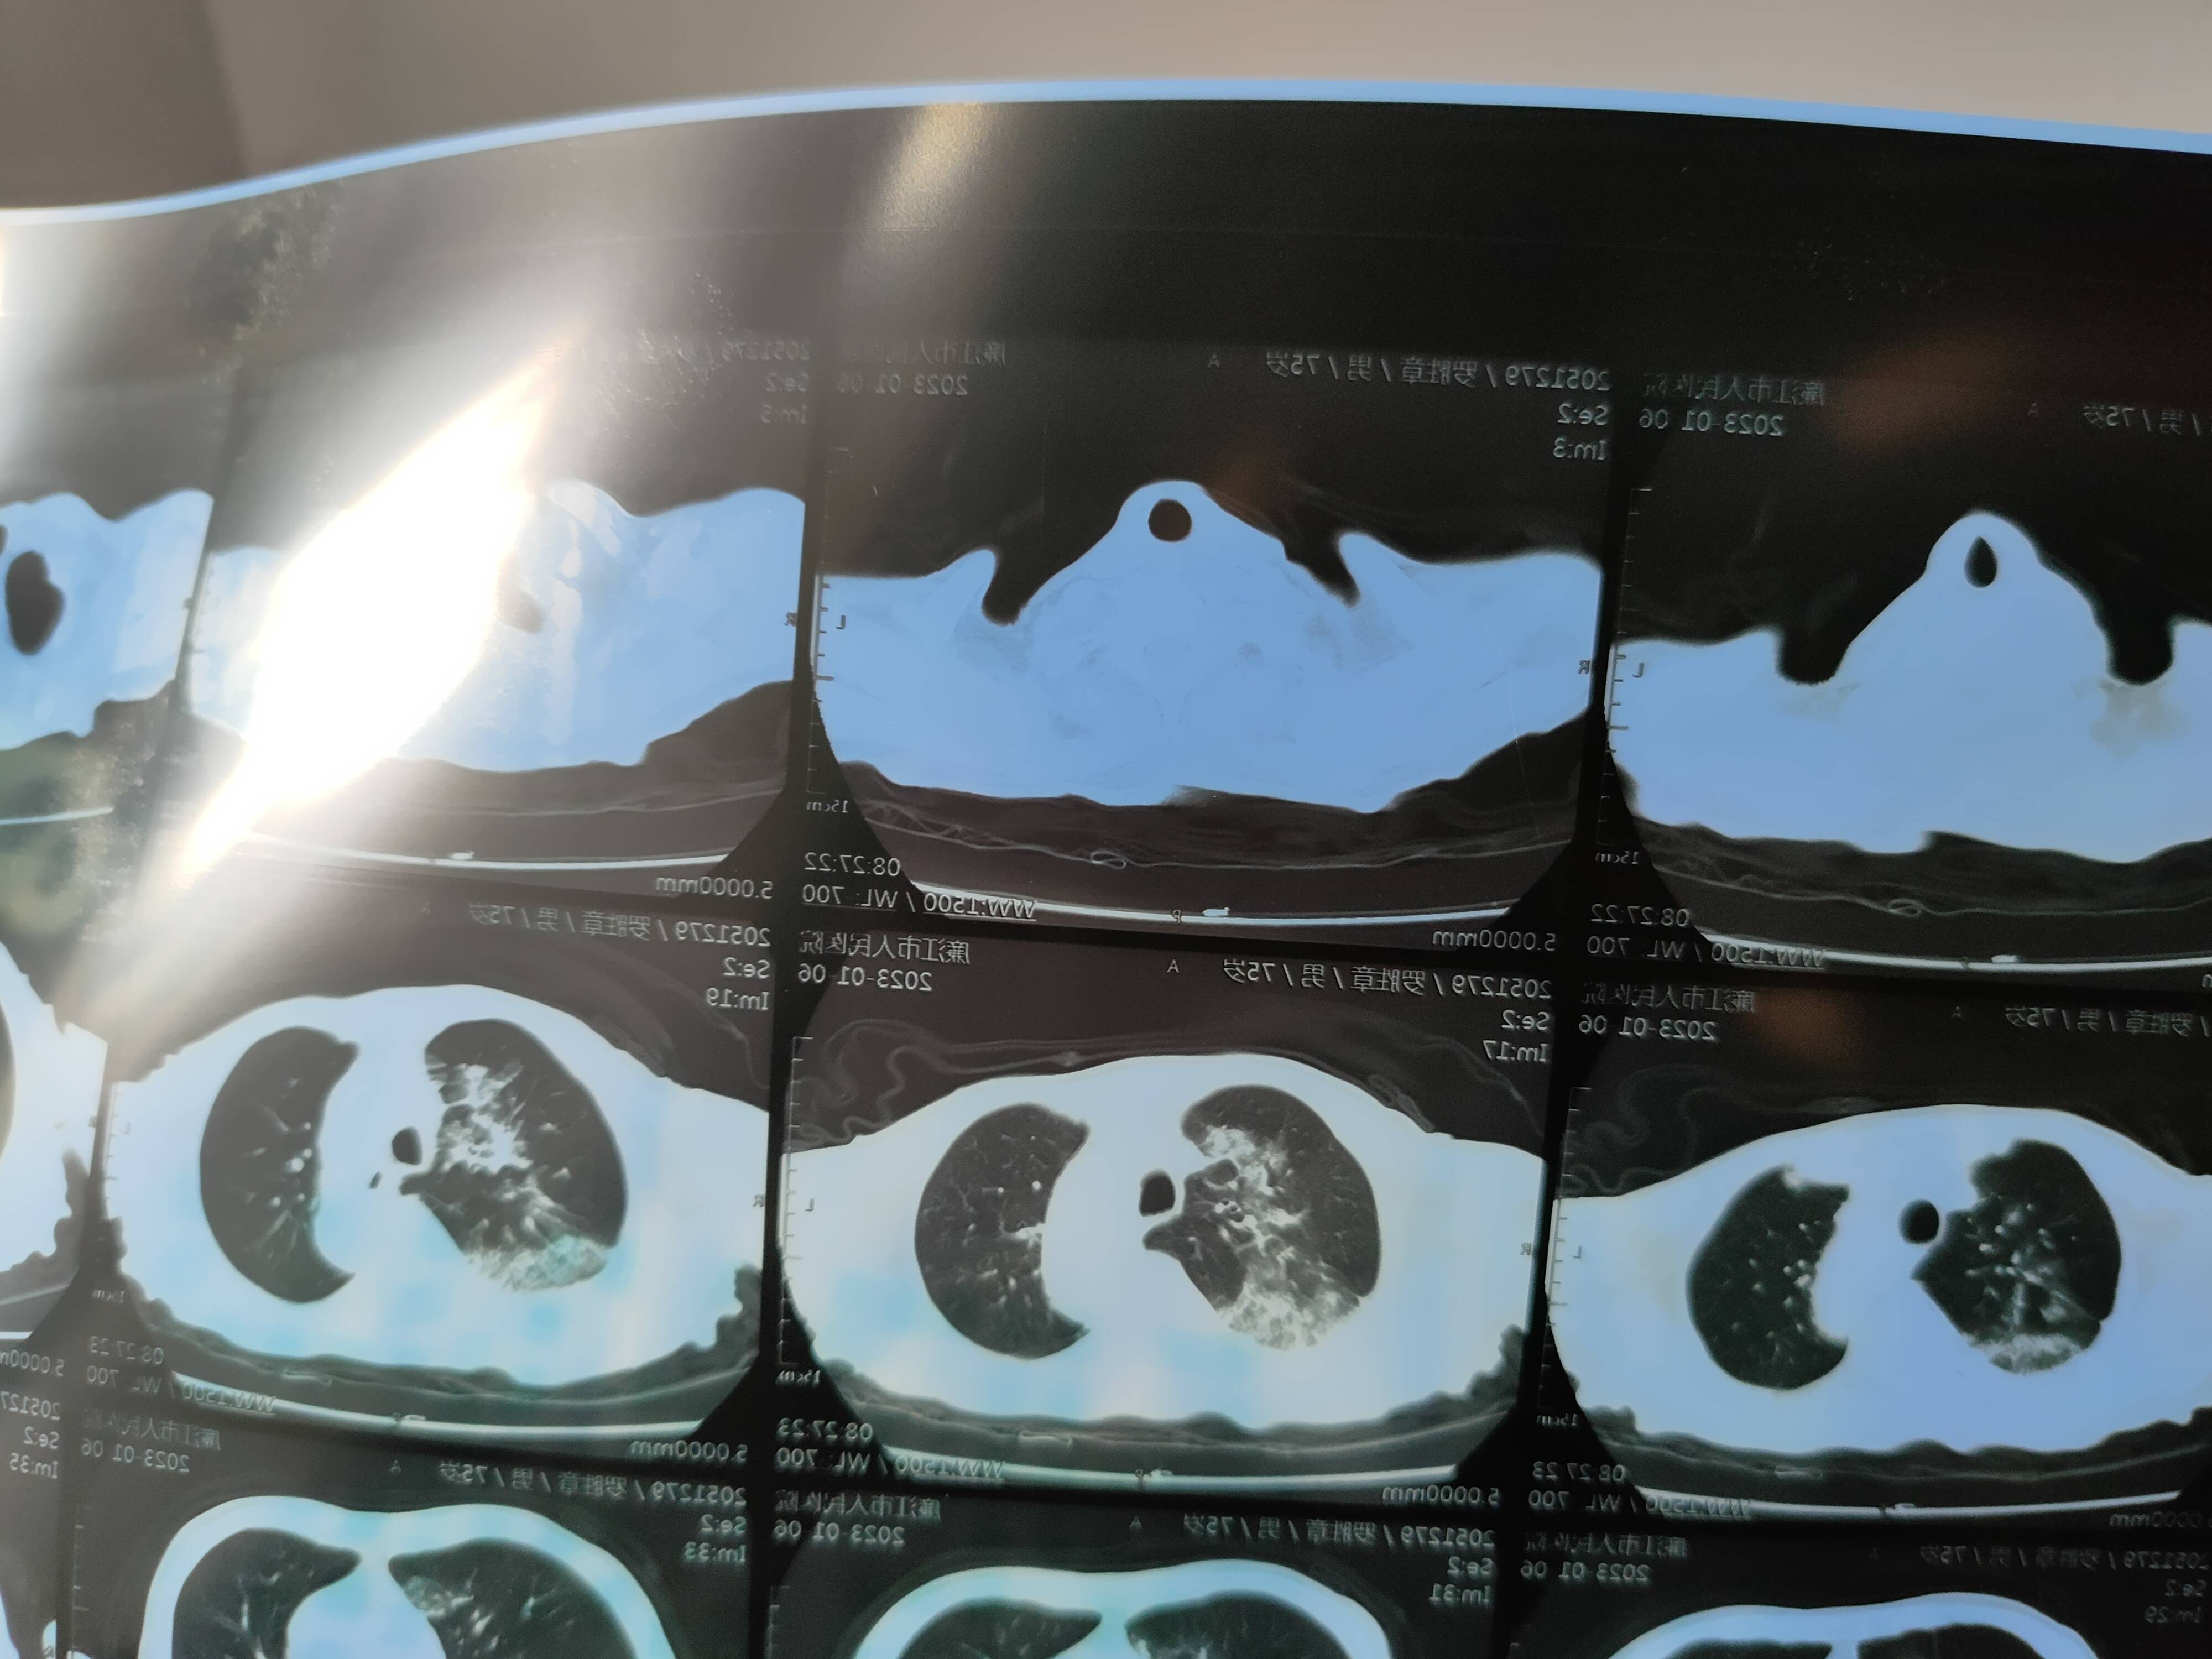

感染新冠肺部有点白,炎症指标低用不了抗生素

怎么样才可以防止肺部继续白面积增大?

应该是病毒感染,如果是阳的五天内可以吃p药,九天内可以试试阿兹夫定。如果买不到这两种药,只能靠自身免疫力,可以打点增强免疫力的药,球蛋白、白介素或者胸腺法新,坚持吸氧还有俯卧位通气。让医生判断下能不能用激素。